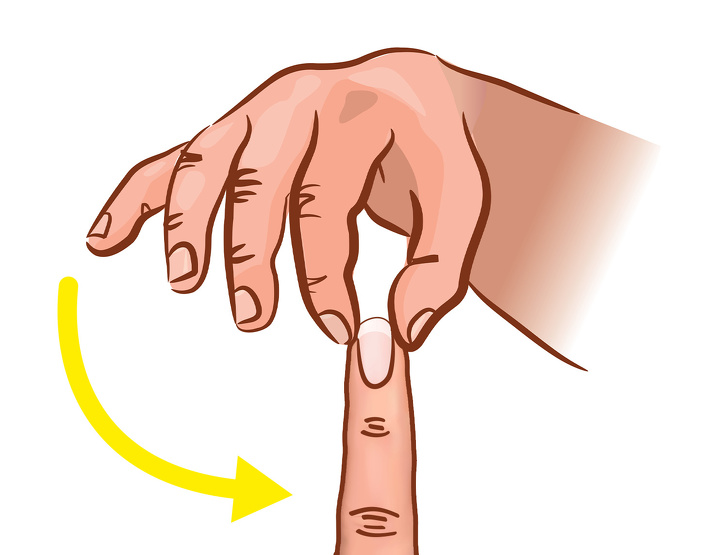

اضغط على جذور الظفر بحزم

قم بالضغط بواسطة الإبهام الأيمن وإصبع السبابة على الجزء العلوي من أصابع يدك اليسرى عبر الضغط على جذور الأظافر،ابدأ بإبهامك مع الاستمرار لمدة 3-5 ثوانٍ، بعد ذلك انتقل إلى الأصابع الأخرى وكرر نفس الشيء.

بعد إزالة الضغط يجب أن يعود الدم سريعًا خلال ما لا يزيد عن ثانيتين، إذا كان الأمر كذلك، فإن جسمك لديه تدفق دم كاف.

وترتبط أصابعك ارتباطًا وثيقًا بأعضائك الداخلية، فإذا كان الاختبار أعلاه مؤلمًا لك، فقد يكون هناك خطأ ما، إليك ما يعنيه الألم في الأصابع المختلفة، وفقًا للخبراء:

الإبهام: إذا كان الضغط على أظفر الإبهام مؤلمًا لك، فقد تكون هذه علامة على وجود مشكلة في الرئة.

يرتبط إصبع السبابة ارتباطًا وثيقًا بأمعائك الغليظة، والألم في هذا الإصبع هو مؤشر على مشاكل القولون والإمساك.

الإصبع الأوسط: يعد ألم إصبعك الأوسط علامة على وجود مشاكل في القلب.

إصبع الخاتم “البنصر”: يرتبط إصبع الخاتم بشدة بقلبك، وإذا كان الضغط على الجزء العلوي منه مؤلماً لك، فقد يكون ذلك علامة على وجود مشاكل في القلب.

الإصبع صغير: يشير ألم إصبعك الصغير إلى مشاكل في الأمعاء الدقيقة.